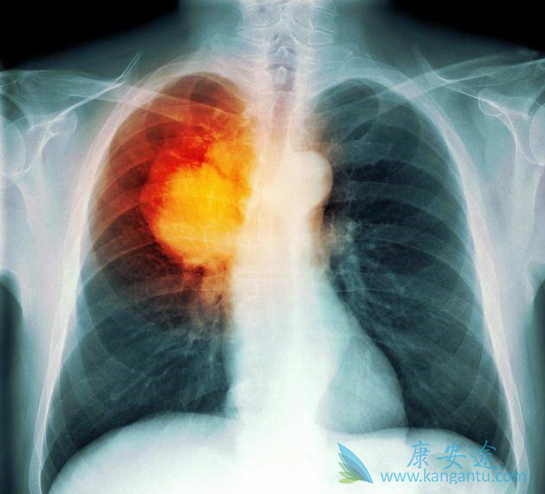

在目前已经公布的不同EGFR-TKI治疗晚期肺癌的III期临床研究中,药物性肝损伤(DILI)的发生率为5%-55.3%,≥3级的发生率为0.4%-26.3%。除阿法替尼外,多数EGFR-TKI主要通过肝脏酶系代谢。有研究认为EGFR-TKI的肝毒性与其活性代谢产物的代谢有关,而诱导的自身免疫性损伤是EGFR-TKI肝毒性的另一种机制。